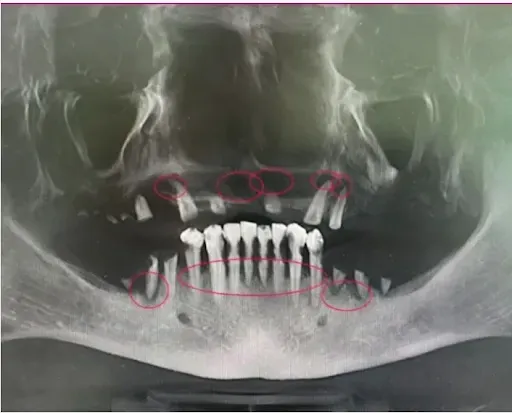

Zdjęcie CBCT/tomografii szczęki z widocznymi ciemnymi obszarami infekcji w kości

Infekcja w kości szczęki

Drugi skan tomografii z dramatyczną różnicą - osoba, która zwlekała za długo

Powyższe zdjęcie pokazuje zaawansowaną infekcję (ciemne obszary tam, gdzie powinna być zdrowa kość). Ta osoba zwlekała zbyt długo i nie kwalifikuje się już do implantów - skazana jest na tradycyjną protezę do końca życia.

ODBUDOWA KOŚCI, IMPLANTY ZYGOMATYCZNE I INNE SKOMPLIKOWANE PRZYPADKI

Jeśli masz znaczny zanik kości, możesz wymagać specjalnych zabiegów chirurgicznych, które wiele klinik traktuje jako dodatek do głównej ceny zabiegu. Poniższy materiał wyjaśnia dokładniej, na czym takie zabiegi polegają.